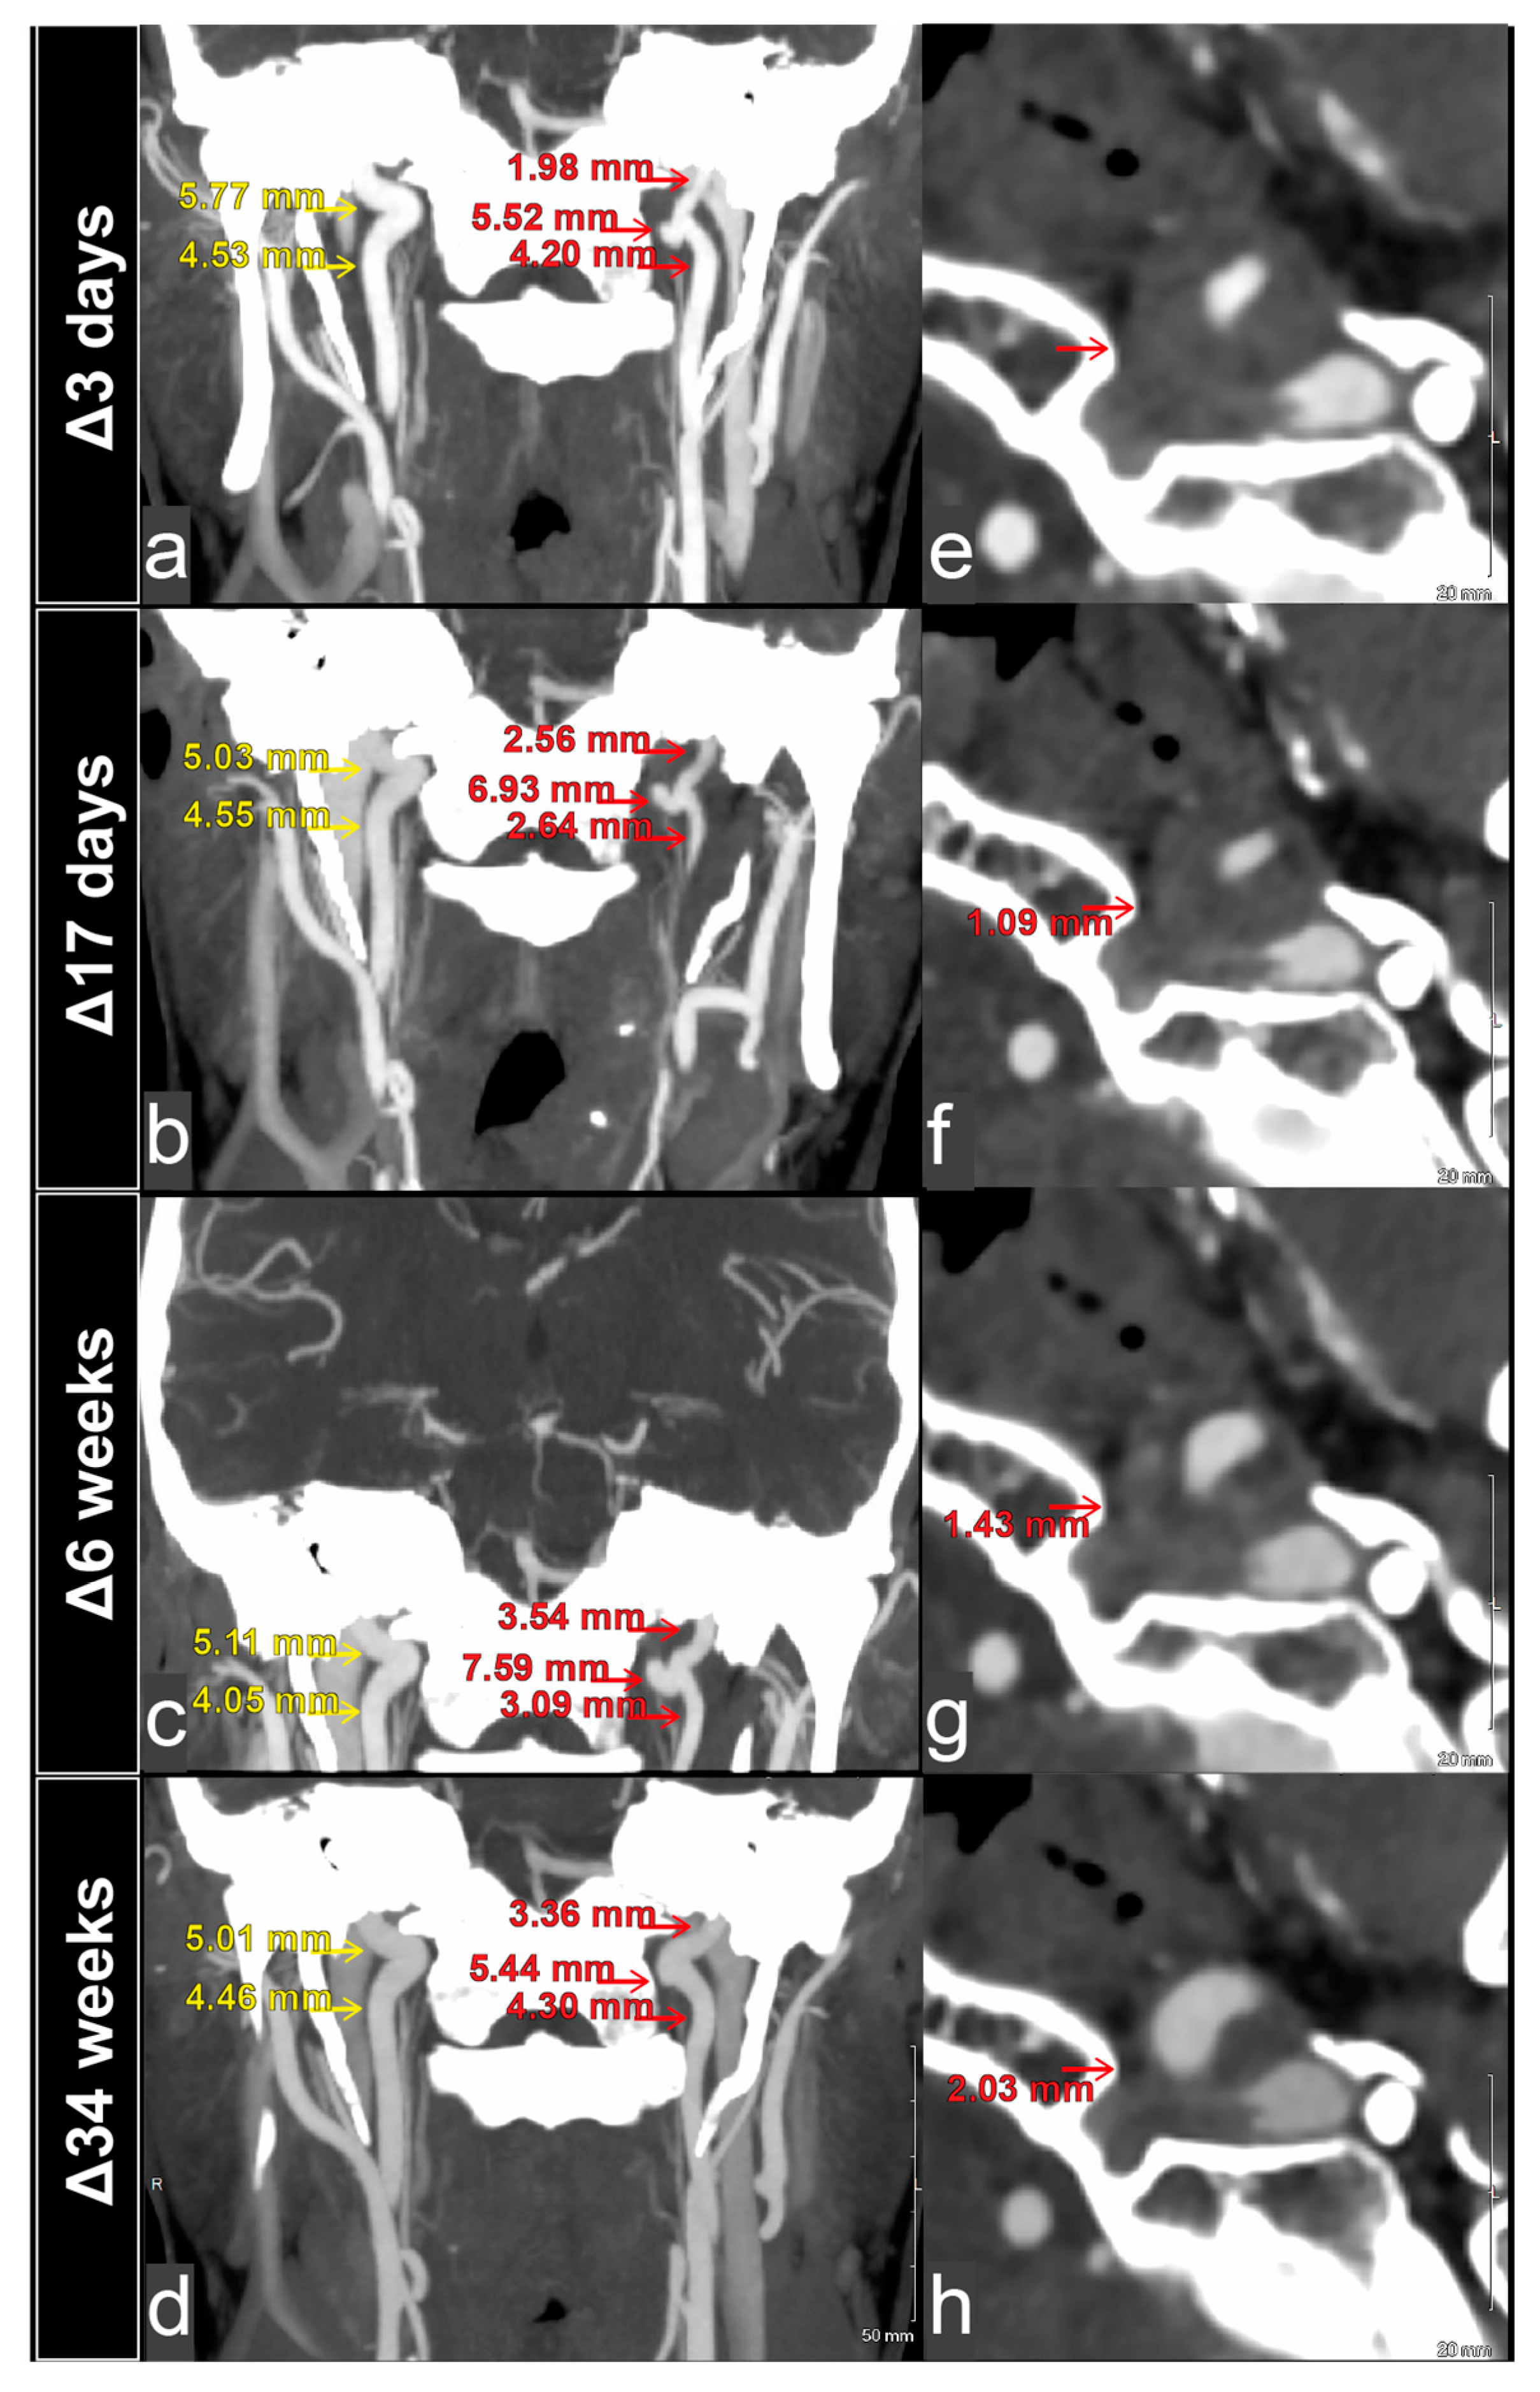

2.1. Initial Presentation

2.2. Two-Week Follow-Up Visit

2.3. Six-Week Follow-Up Visit

2.4. Six-Month Follow-Up Visit